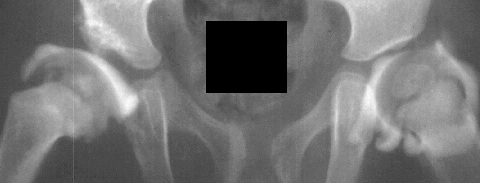

At 5 + 8 years of age

,

a clinical diagnosis of Charcot-Marie-Tooth disease was made, and Shelf

arthroplasty was performed to increase the femoral head coverage.

On the last evaluation (10 years old), the patient was pain free, and showed

acceptable range of motion, however, his right limb is 3 cms. short and

the patient is wearing a 2 cm. shoe lift.